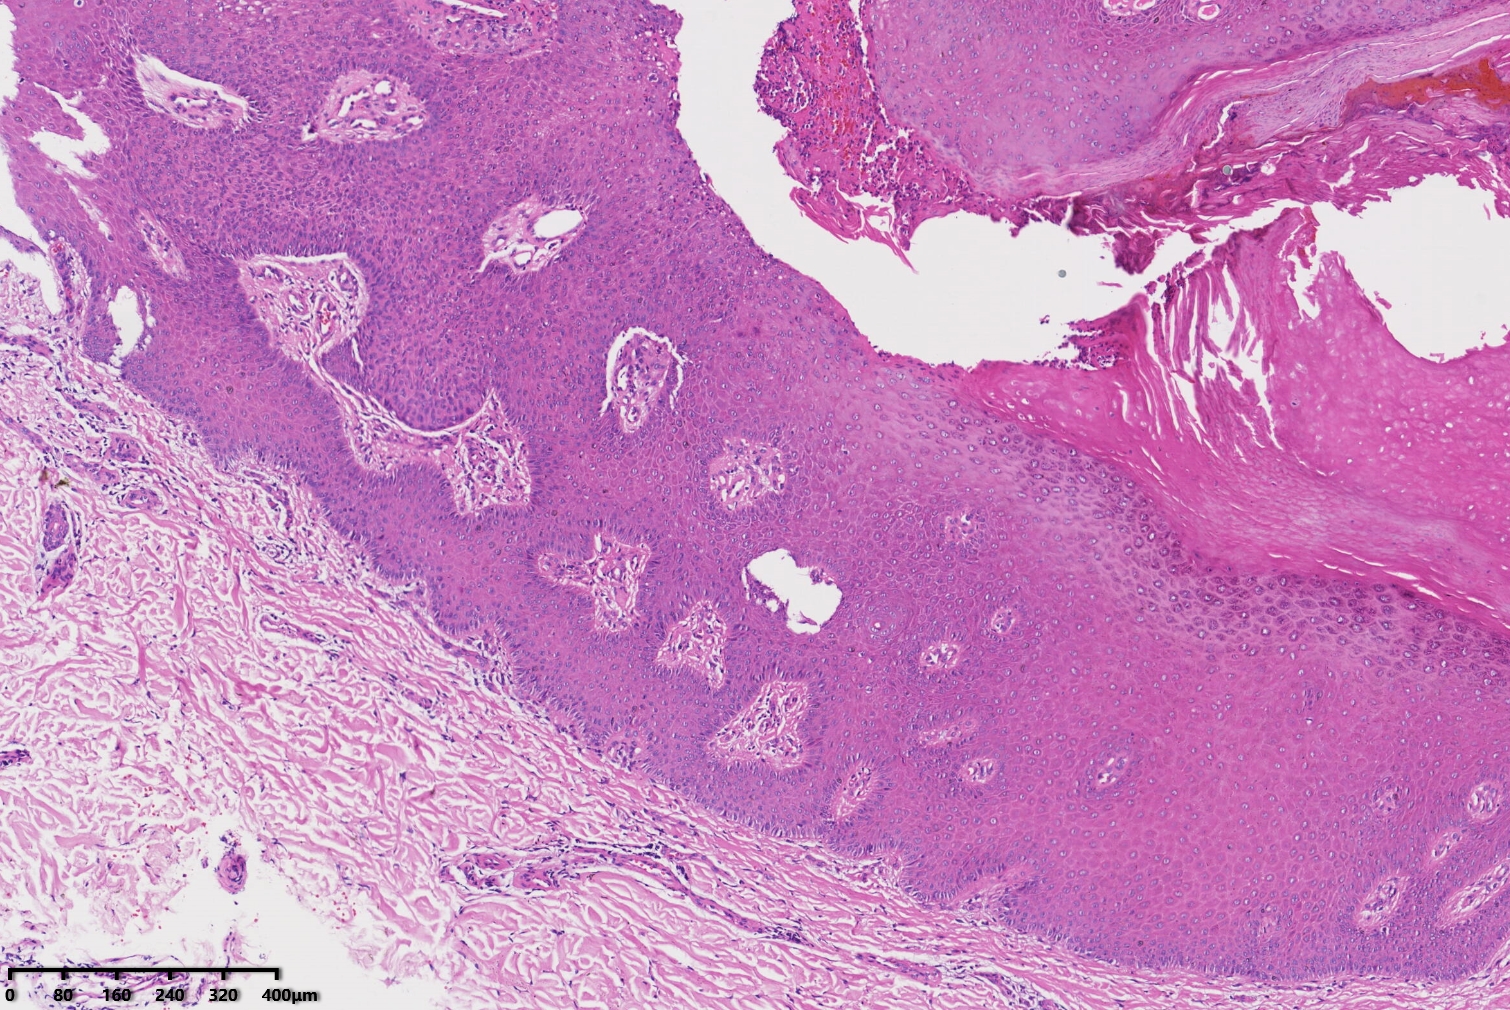

汗孔瘤?

性别

女

年龄

53岁

左足部皮肤包块

汗孔瘤。

脂溢性角化病